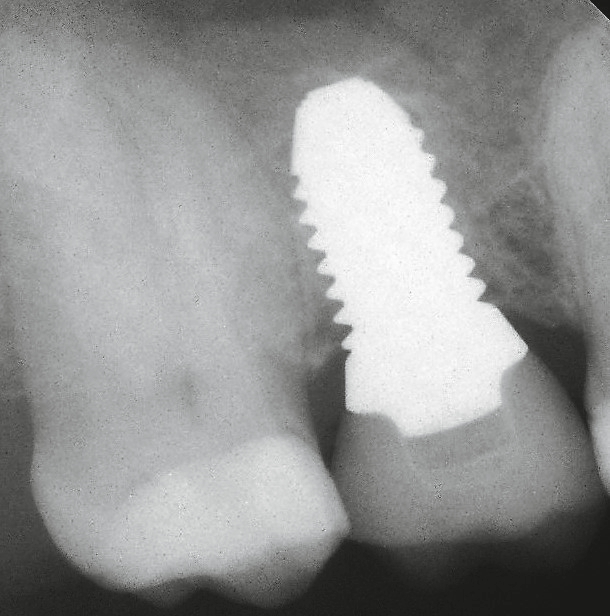

Ob Champions Zirkon-BioWin! (Abb. 9) oder Titan (R)Evolution Implantat (Abb. 11): Das aufbereitete Grinder-Zahnmaterial (Abb. 10) wird beim internen, direkten Sinuslift (IDS) erfolgreich, minimal- invasiv (MIMI Vb) und ohne Komplikationsgefahr mit abgerundeten Condensern und mit linksdrehendem, abgeflachtem 3,7 mm D Krestalbohrer unterhalb der Membran eingebracht.

Der („unblutige“) IDS benötigt nur wenige Minuten. Auf den Kontrollröntgenbildern sieht man deutlich „die Wolken“ des Grinder Materials, welches definitiv zu Knochen umgewandelt wird.